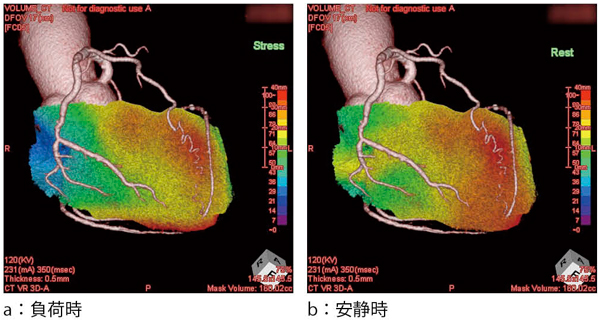

図5 CT-SPECT Fusion Imaging

図6 CT-SPECT Fusion Imaging

LAD領域の梗塞+虚血性変化(peri-infarct ischemia)を認める。

これらの結果から,ザイオソフト社製ワークステーション「ZIOSTATION」の「CT/SPECT心臓フュージョン」ソフトウェアを用いて,CT-SPECT Fusionの画像構築を行ったところ,RCA#3の残存狭窄病変に一致する虚血とLAD#6のCTO病変に一致する梗塞+虚血性変化が認められた(図5,6)。CT-SPECT Fusionの結果から,残存病変に対する血行再建の必要性が考慮され,回復期にCAGを行った(図7)。再検したCAGにおいて,LADのCTO病変に関してはPCI困難と判断された。RCAのステント留置部位に関しては亜急性期の再狭窄は認めなかったが,末梢側に有意狭窄を認め,LCX

#14の高度狭窄病変と合わせ,いずれもCTCAと同様の所見であった。以上から,冠動脈バイパス手術(CABG)による血行再建が最適と判断され,第27病日に冠動脈3枝に対しCABGを施行した。

本症例ではCT-SPECT Fusion Imagingにより,残存する虚血領域と責任病変の同定が視覚的に容易に診断され治療方針決定に有用であった。今回使用したザイオソフト社製のFusionソフトウェアは従来のものと比較し,短時間での重ね合わせが可能で簡便であった。また,得られたFusion画像は患者や家族にバイパス手術の必要性を説明し同意を得る際にも活用でき,スムーズに治療を進める上でも効果的であった。